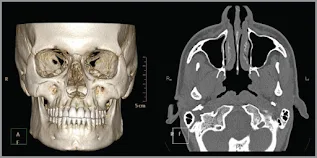

Tomodensitometrie (scanner) et Cone Beam

La TDM explore particulièrement bien la région condylienne. La TDM en incidence axiale, avec reconstruction coronale et sagittale, est indiquée lors des fractures plurifocales et associées.